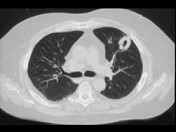

- 单项选择题男,45岁, 胸痛,咳嗽, 咳痰半月余,发热, 既往有副鼻窦炎病史,CT检查如图, 选择最可能的诊断 ( )

A、结节病

B、周围型肺癌

C、韦格肉芽肿

D、肺转移瘤

E、结核球